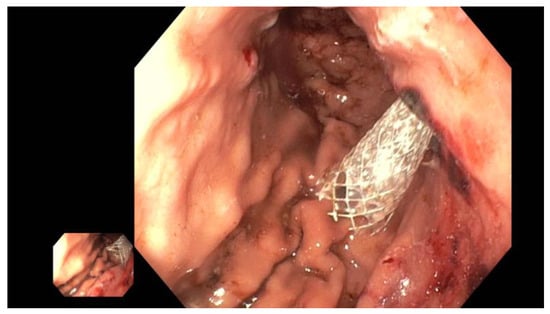

(B) EUS-guided pancreatic duct drainage (EUS-PD): If the wire cannot pass through the papilla or if the papilla is unreachable with a standard duodenoscope or enteroscope (e.g., post-gastrectomy, Roux-en-Y reconstruction, Kausch–Whipple surgery; see the above), the wire is advanced as far as possible into the pancreatic duct following an EUS puncture. An access site is then created along the wire using a Will HF ring knife (MTW Endoskopie Manufaktur W. Haag KG, Wesel, Germany) followed by dilatation of the typically transgastric access using a 6-mm bile duct dilatation balloon (Boston Scientific, Ratingen, Germany). The choice of prosthesis, which is inserted, depends on factors such as the site and width of the pancreatic duct system or the direction of the puncture. If a wide pancreatic duct is punctured near the obstruction, antegrade drainage (pancreaticogastrostomy/pancreaticoduodenectomy) can be attempted by using a self-expanding metal stent (SEM or LAMS, Boston Scientific, Ratingen, Germany) or a straight plastic Amsterdam prosthesis (Medi-Globe, Achenmühle, Germany) (Figure 5).

Figure 5. Dilated pancreatic duct (red arrow) in history of necrotizing pancreatitis—suspected DPTS; EUS-guided pancreatography (left panel) with following insertion of a plastic prosthesis (red arrow) for retrograde drainage (middle panel) and endoluminal (endoscopic) control of the right plastic prosthesis position (red arrow—right panel); selected from the clinical picture library of the reporting Dept. of Gastroenterology, Hepatology and General Internal Medicine.